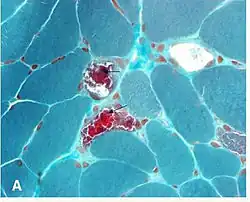

Gömöri trichrome stain

Gömöri trichrome stain is a histological stain used on muscle tissue.[2][3]

It can be used to test for certain forms of mitochondrial myopathy.